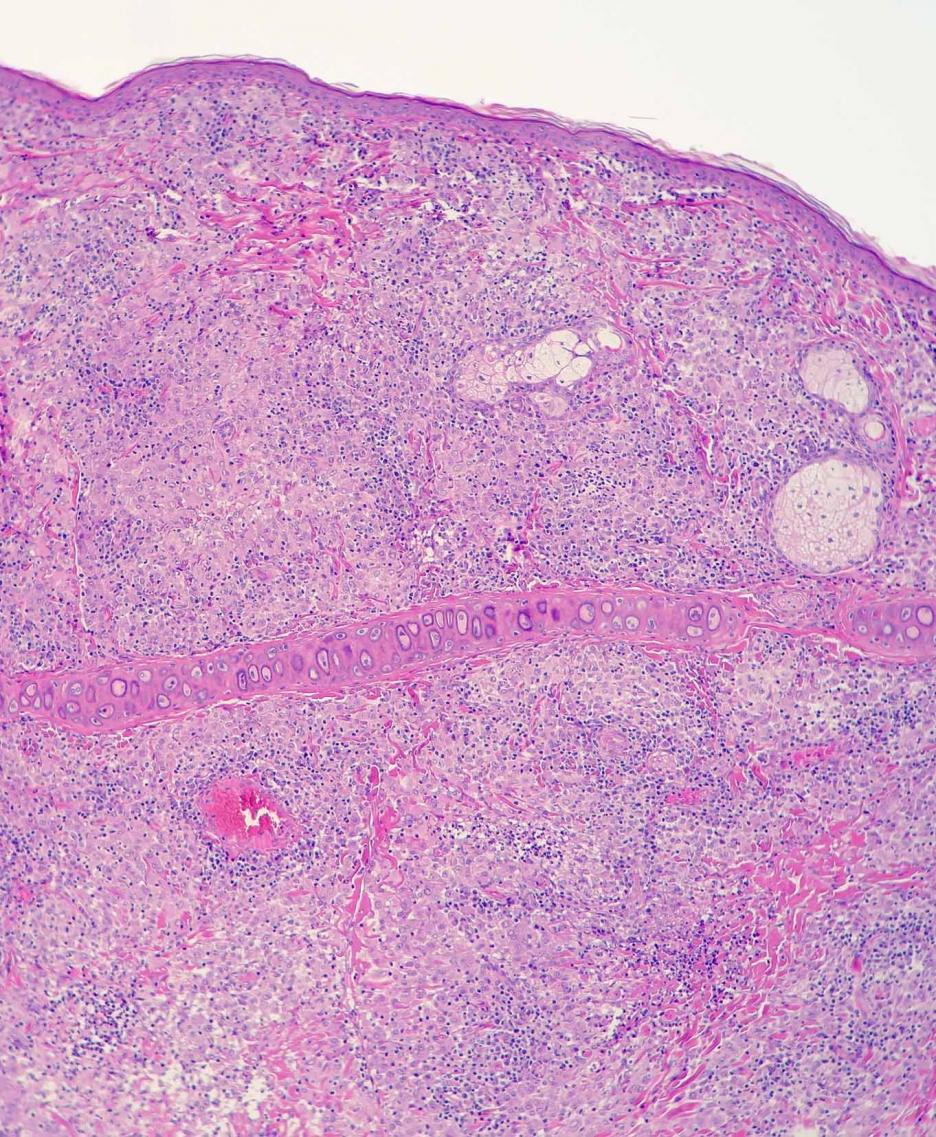

Leishmaniasis en hurón

Ésta es la primera descripción de leishmaniasis en un hurón, eficaz y diligentemente trabajada, como siempre, por Jacobo Giner de Centro Veterinario Menescalia, con la colaboración de la Universidad de Zaragoza y publicada en Veterinary Parasitology: Regional Studies and Reports 19:100369, 2020. doi: 10.1016/j.vprsr.2020.100369. Con esta publicación, Jacobo logró el 2º premio de los Premios de Divulgación Científica 2020 del Ilustre Colegio de Veterinarios de Valencia; aunque Jacobo está acostumbrado a ganar premios y seguro que tiene entre ceja y ceja el primer premio, nuestras más sinceras felicitaciones por este extraordinario logro y ánimos para que siga persiguiendo el primer premio y así pueda invitarme a esas cenas que me debe en el restaurante de cocina de autor Almoraduz, Puerto Escondido (Oaxaca). No se pierdan el taller de Medicina y Patología de Hurones del Congreso Solidario de Medicina y Conservación de Fauna Exótica y Salvaje de Puerto Escondido con Jacobo, Mike Garner y un servidor, va a ser extraordinariamente rico en medicina, patología y humor...cuando de una vez por todas podamos celebrar este congreso. ¡Bravo, Jacobo!.